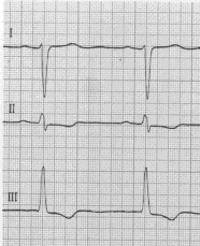

Ermittlung der höchsten Zacke:

Abl. I => Linkstyp

Abl. II ist positiv

Abl. III überwiegend negativ